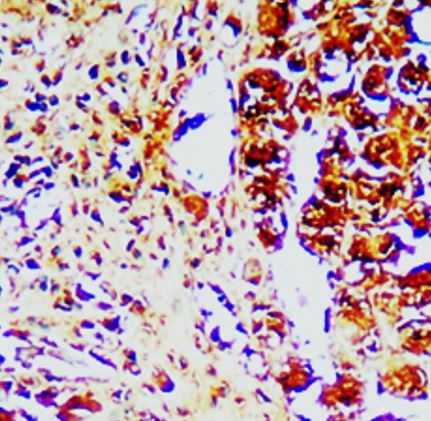

ARG66963 anti-Caspase 8 antibody IHC-P image

Immunohistochemistry: Human Hepatocellular Carcinoma stained with ARG66963 anti-Caspase 8 antibody.